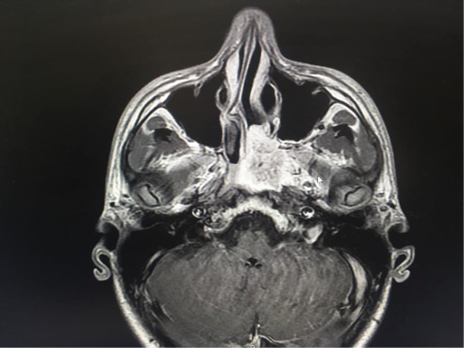

Resonancia Magnética Nuclear de senos paranasales contrastada con hallazgos masa hipointensa en secuencias T1 que realza ávidamente con la aplicación del medio de contraste de 38 x 35 mm que presenta señal de vacío en su interior, ubicado en la coana izquierda, infiltra el seno esfenoidal, el musculo pterigoideo interno, el tejido adenoideo a la altura del cavum faríngeo y erosiona la apófisis pterigoides ipsilateral. (Figura 3).

Figura 3. Resonancia Magnética Senos paranasales T1. Fuente: Hospital Militar Central de Bogotá.